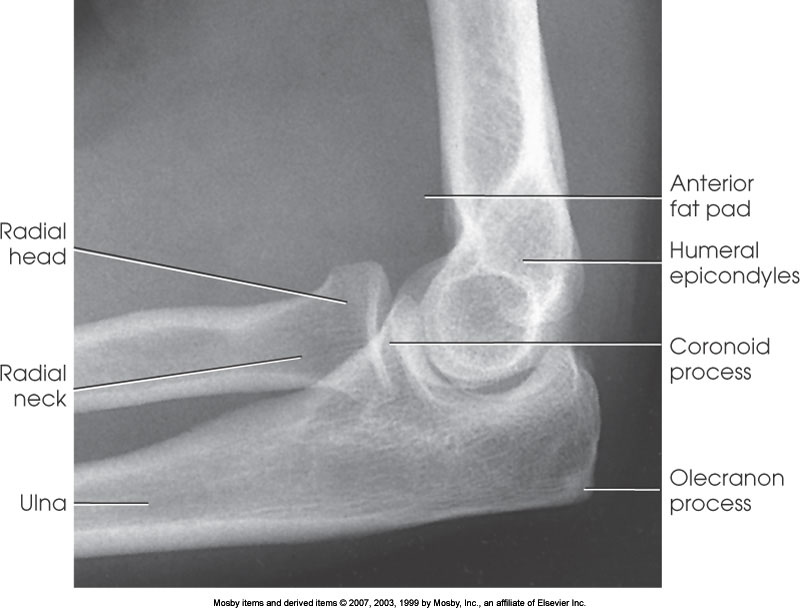

Lateral Elbow